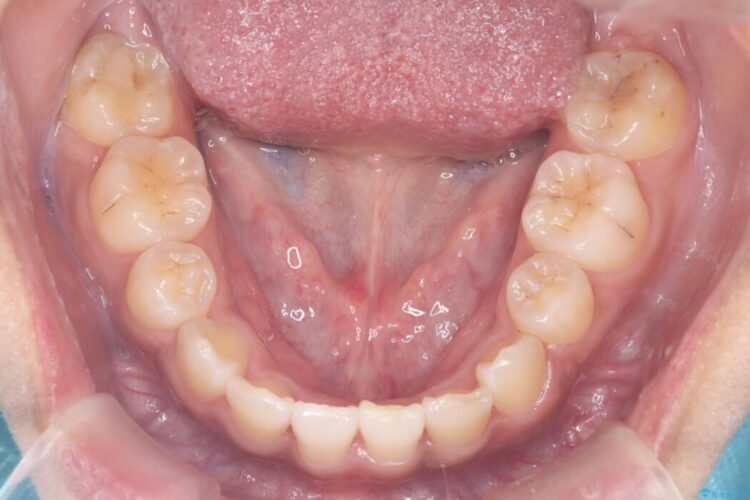

矯正検査の結果、歯列全体のスペースが不足しており、これが突出感の原因となっていました。

無理に歯を並べても口元の突出感は解消されないため、上下左右4番を抜歯しスペースを確保、目立ちにくい審美ワイヤー装置にて治療を行うこととしました。